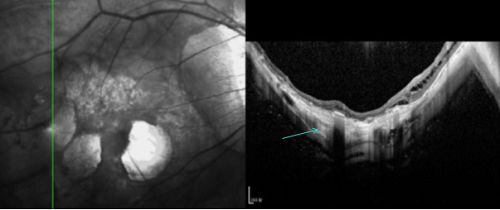

§ 高度近视患者

临床上,通常把近视度数超过600度称为高度近视。高度近视患者的眼轴比普通人更长,视网膜随着眼轴的变长而被牵拉变薄,发生黄斑出血、周边视网膜变性、视网膜裂孔、视网膜脱离等的概率也比正常人高。

▲高度近视视网膜病变

▲眼轴拉长,视网膜脉络膜变薄,萎缩